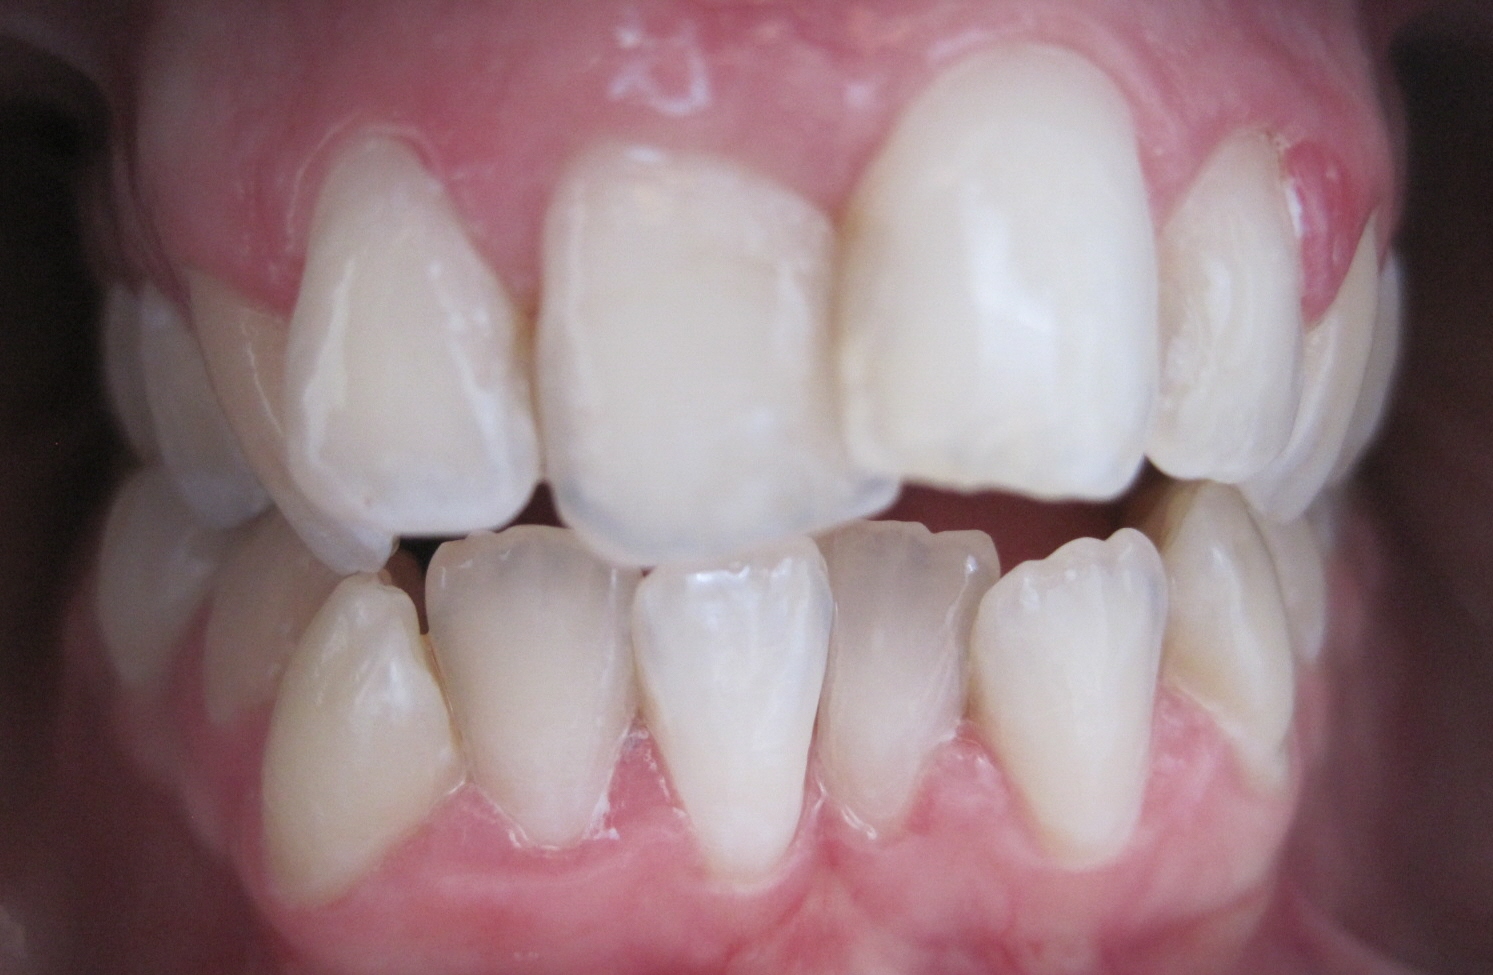

Patient 41 Jahre, massiver Unterkiefer-Frontzahn-Engstand: Alphalignbehandlung mit 15 Alphalignern, d.h. 7,5 Monate Behandlungszeit, jetzt viel bessere Pflege möglich, da akkurater Zahnbogen, dadurch geringeres Risiko von Karies sowie Zahnfleisch- und Zahnbetterkrankungen

vorher